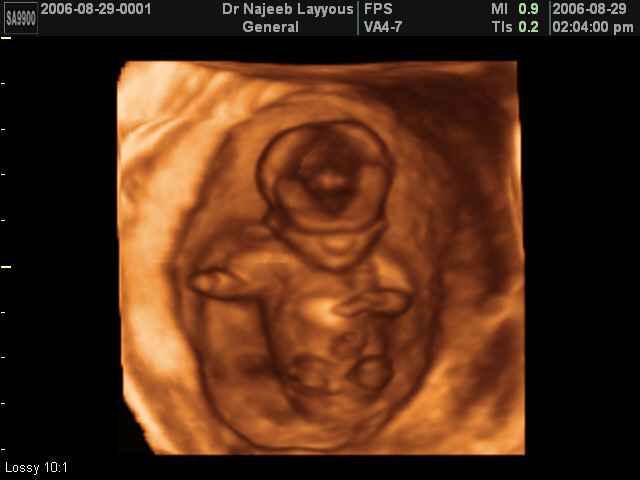

3D First Trimester Ultrasound Scan Photos